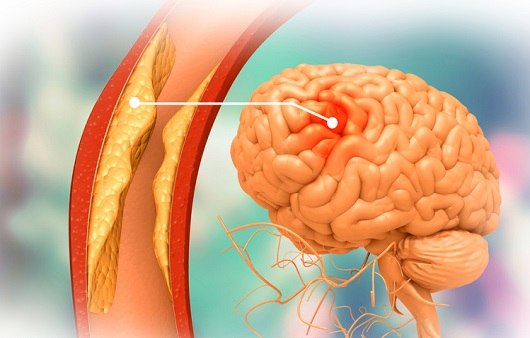

뇌혈류 감소가 일정 시간 이상 계속되면 뇌조직의 괴사가 시작되어요. 뇌조직이 괴사 되어 회복 불가능한 상태에 이르렀을 때 이를 뇌경색이라고하고요. 반면 뇌혈류 감소에 의해 뇌기능에 이상이 생겼지만, 적절한 치료를 통해 넉넉한 뇌혈류가 다시 보급되어 뇌조직의 괴사 없이 뇌기능이 회복된 경우를 일과성 허혈성 발작이라고 불리워요. 허혈성 뇌졸중은 뇌경색과 일괄성 허혈성 발작을 모두 다 포함해서서 일컫는 용어이예요.

뇌조직은 평소에도 거량 물량의 피를 공급받고 있고요. 근데 수많은 이유으로 인해서 뇌혈관에 혈관 등을 이루는 관이 막히는 경우가 일으켜서 뇌에 공급되는 혈액량이 줄어들게 보면 뇌조직이 기능을 정확히 하지 못하게 돼요.

동맥경화증을 방지하기 위하여 콜레스테롤이 높은 식품은 피하며, 가공음식, 인스턴트음식 또한 가급적 지양하고 염분의 양이 많은 식품은 피해요. 또한 금연, 금주하며, 고혈압과 뇌졸중 예방을 위해서 염분 섭취를 감소시키는 것이 중요해요. 그리고 연쇄적인 운동으로 혈압을 느슨하게하고 비만을 방지해요.